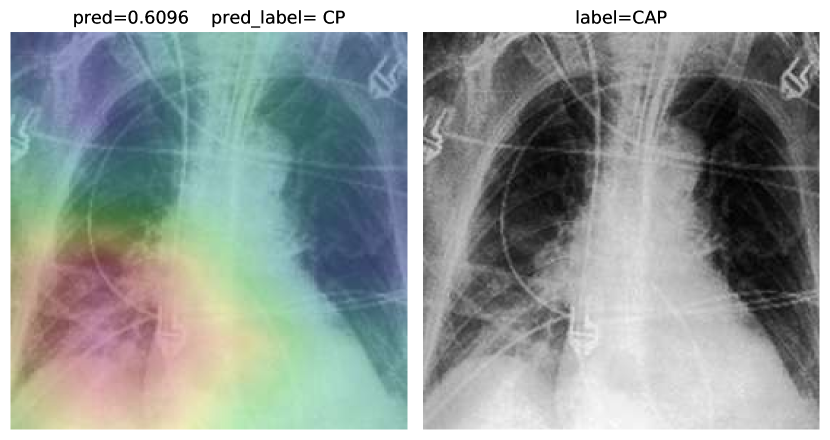

Accuracy score is 81.04%, with f-scores of 0.85 and 0.76 for CP and CAP classes, respectively. In a number of cases, especially in the first stages of virus progression, CP has unilateral findings. Also, CAP may cause bilateral consolidations. Therefore, some cases are expected to be misclassified between CP and CAP. From the confusion matrix, it could be seen that a relatively high number of images are misclassified between CAP and normal. A potential reason for this issue is considered to be related to wrong labeling. Besides, some CAP CXRs are from patients with early-stage disease development. To confirm the model performance, Grad-CAMs are plotted in Fig. 19.

Figure 19: COVID-CXNet multiclass classification visualization results

The model is properly looking at one lobe for detecting CAP and both lobes for CAP and normal images. There are some wrong labels, nevertheless. A figure containing more visualizations is found in Appendix C. To further enhance statistical scores, a hierarchical approach is implemented. In the first level, we classify images into normal and pneumonia classes. In the second level, pneumonia images are categorized into CP and CAP. Final confusion matrix is illustrated in Table 5.